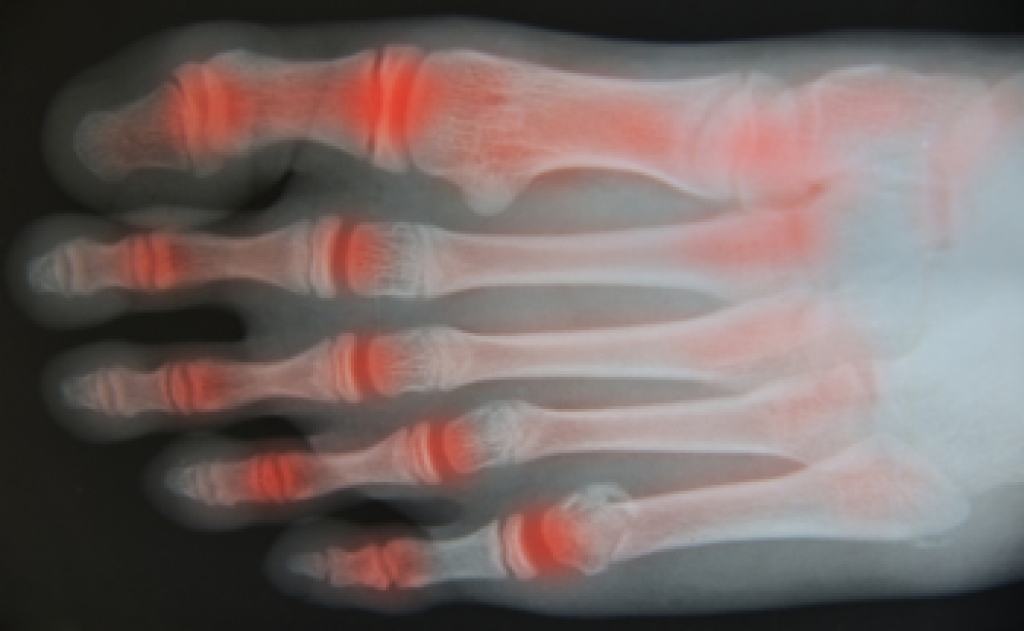

Foot arthritis causes inflammation and pain in the joints of the foot. It occurs when the cartilage that protects the joints wears down, leading to discomfort and limited movement. The two main types of foot arthritis are osteoarthritis and rheumatoid arthritis. Osteoarthritis is the most common form of arthritis and develops over time as the cartilage deteriorates due to age, injury, or wear and tear. Rheumatoid arthritis is an autoimmune disorder where the body’s immune system attacks the joints, causing inflammation and pain. Several factors contribute to the development of foot arthritis, including genetics, previous joint injuries, obesity, and repetitive stress. Symptoms of foot arthritis include joint stiffness, swelling, and difficulty walking. If you have developed foot arthritis, it is strongly suggested that you are under the care of a podiatrist who can guide you toward relief and management techniques.

Arthritis is a joint disorder that involves the inflammation of different joints in your body, such as those in your feet. Arthritis is often caused by a degenerative joint disease and causes mild to severe pain in all affected areas. In addition to this, swelling and stiffness in the affected joints can also be a common symptom of arthritis.